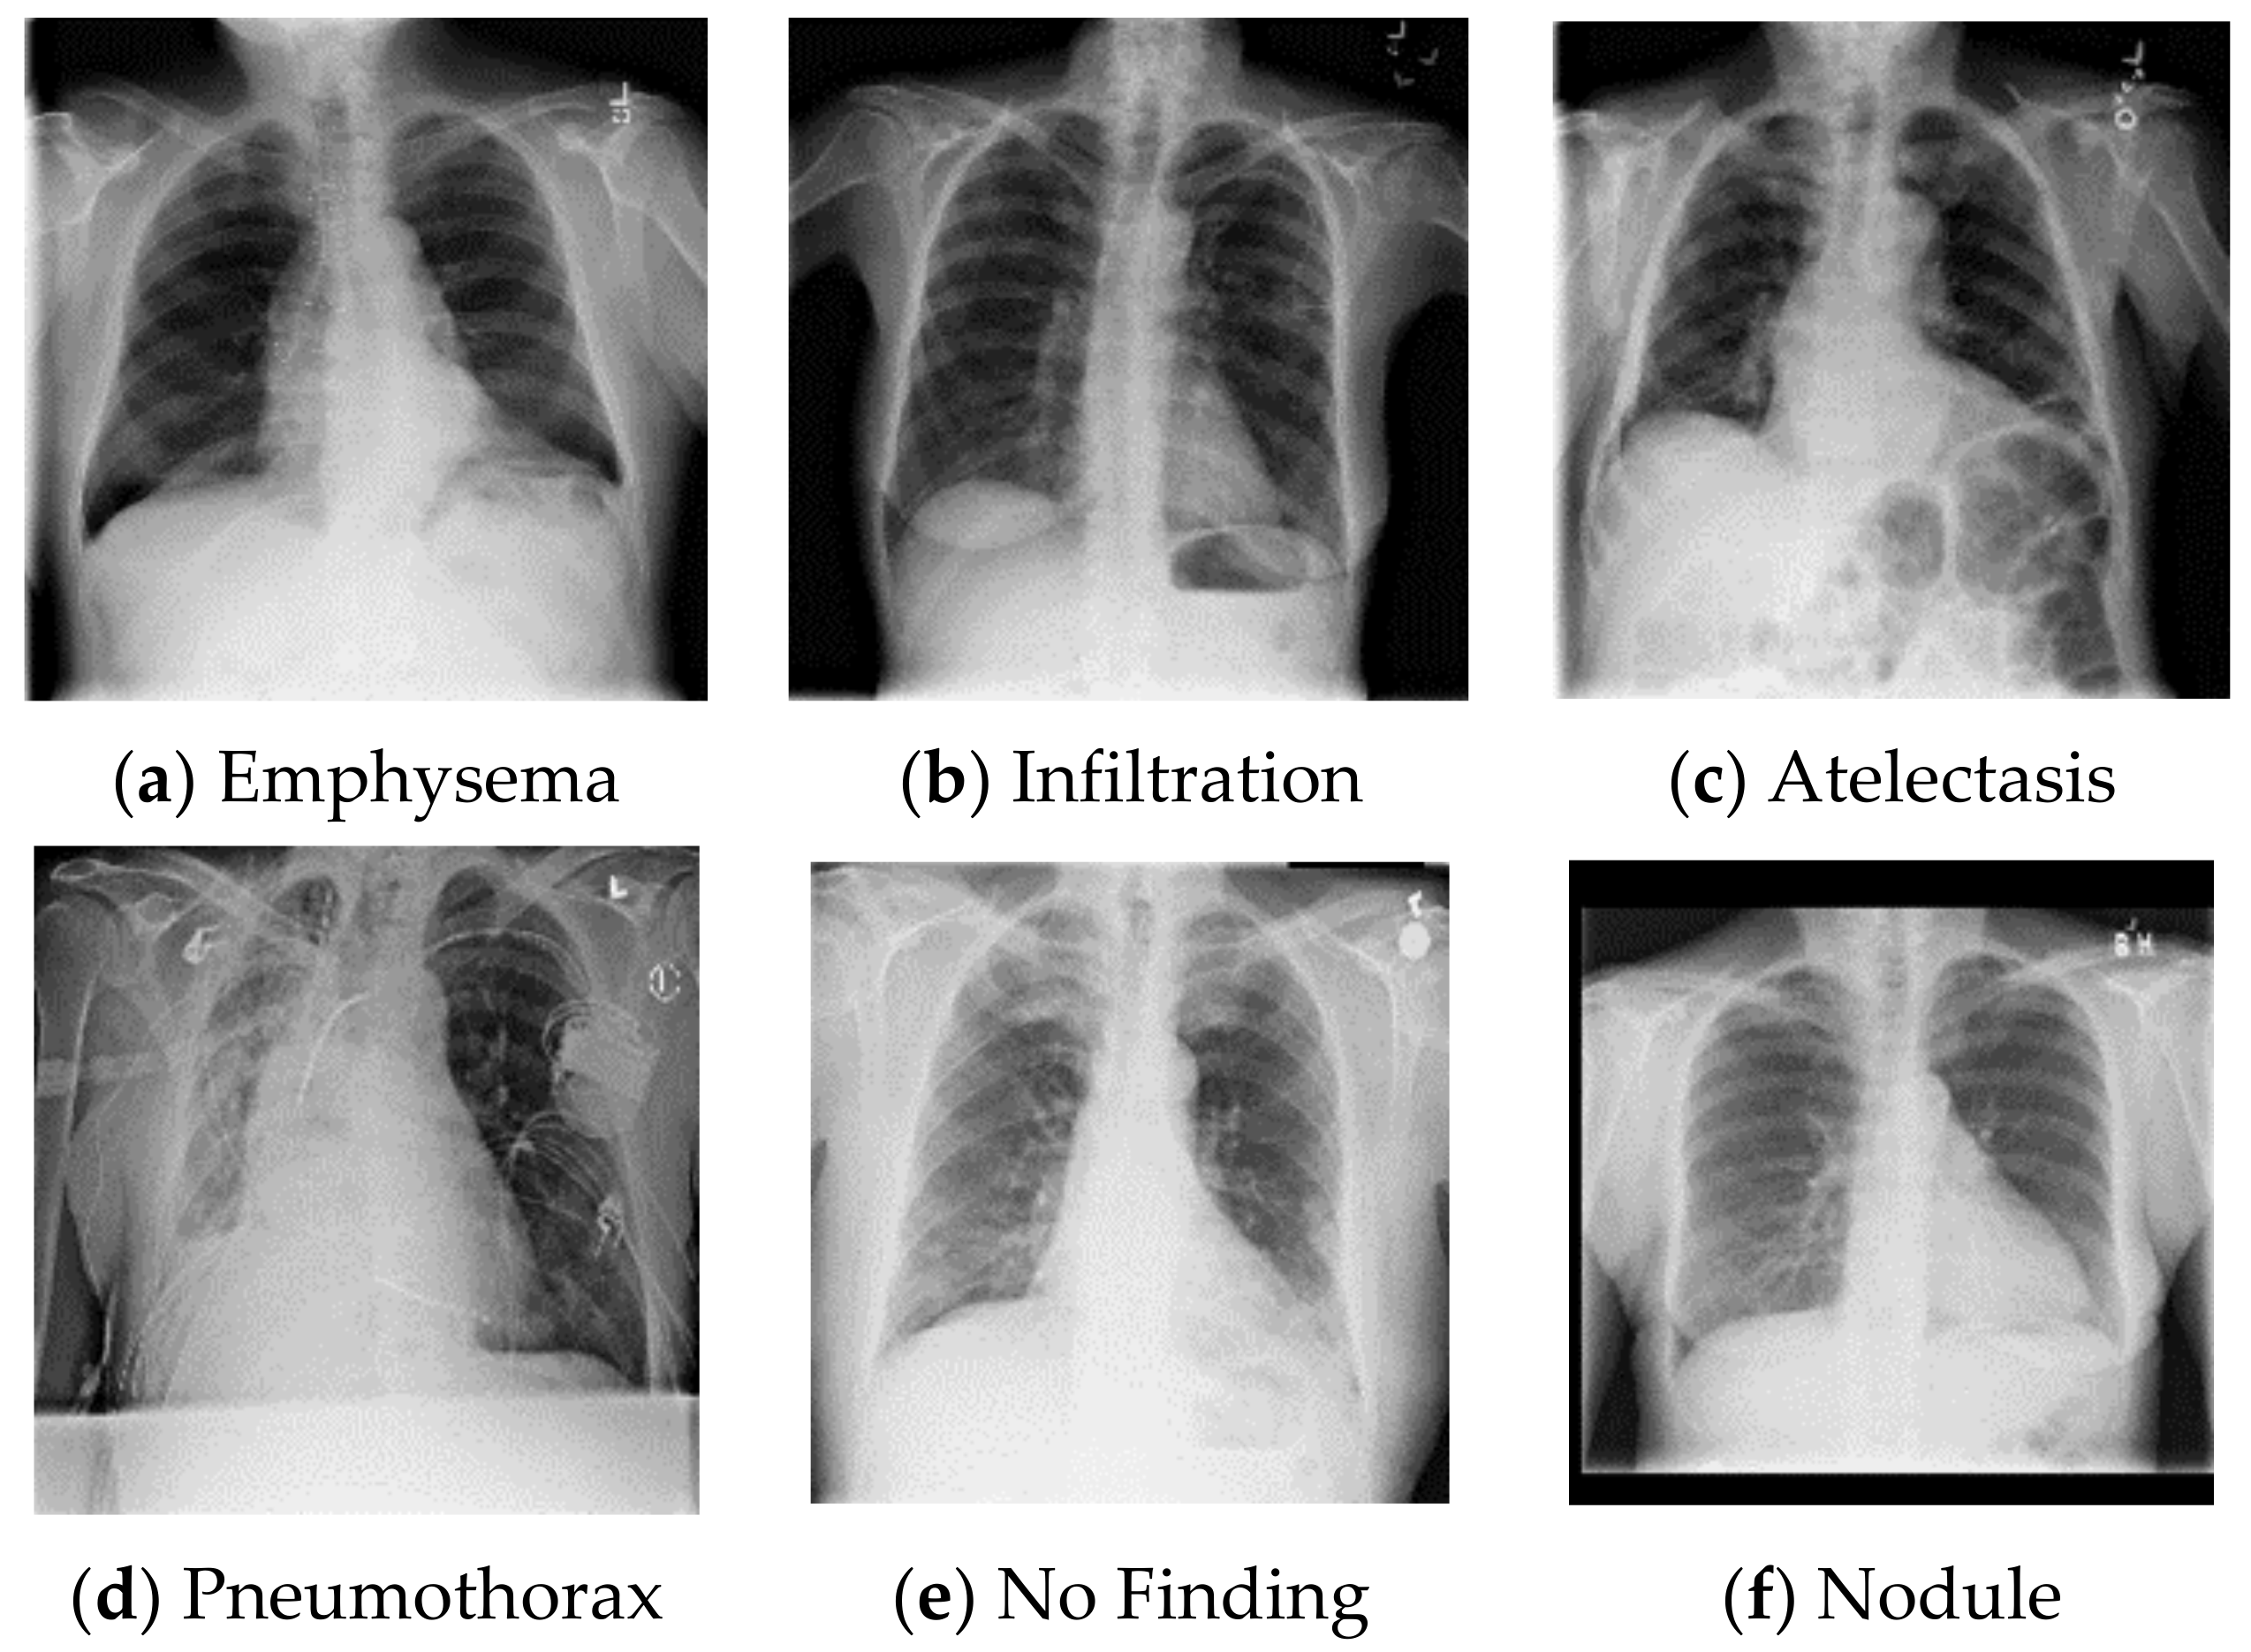

Imgs For Chest X Ray Abnormal

Imgs For Chest X Ray Abnormal